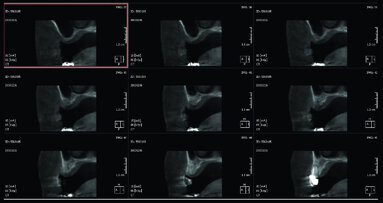

La pneumatizzazione dei seni mascellari ha ridotto notevolmente l’altezza ossea in posizione dei primi molari, tale da non permettere l’inserimento degli impianti se non con una terapia rigenerativa (Figg. 6, 7).

L’alternativa chirurgica adottata prevede il posizionamento di impianti inclinati mesiali alla parete anteriore del seno con emergenza protesica in corrispondenza del primo molare per permettere una riabilitazione senza cantilever distali, sia nel primo che nel secondo quadrante.